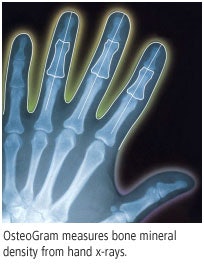

At the RSNA show, bone densitometry and medical informatics firm CompuMed of Los Angeles will feature OsteoGram, its standalone, software-based medical image processing system that allows healthcare providers to screen, diagnose, and monitor osteoporosis using images from analog or digital x-ray equipment.

In February, the company announced that it had linked OsteoGram to digital mammography equipment so that the system can be used as an accessory tool or integrated into a digital workstation, allowing women to be tested for osteoporosis at the same time as their CR or DR exam, or annual mammogram. In September, CompuMed received the European CE Mark for OsteoGram.